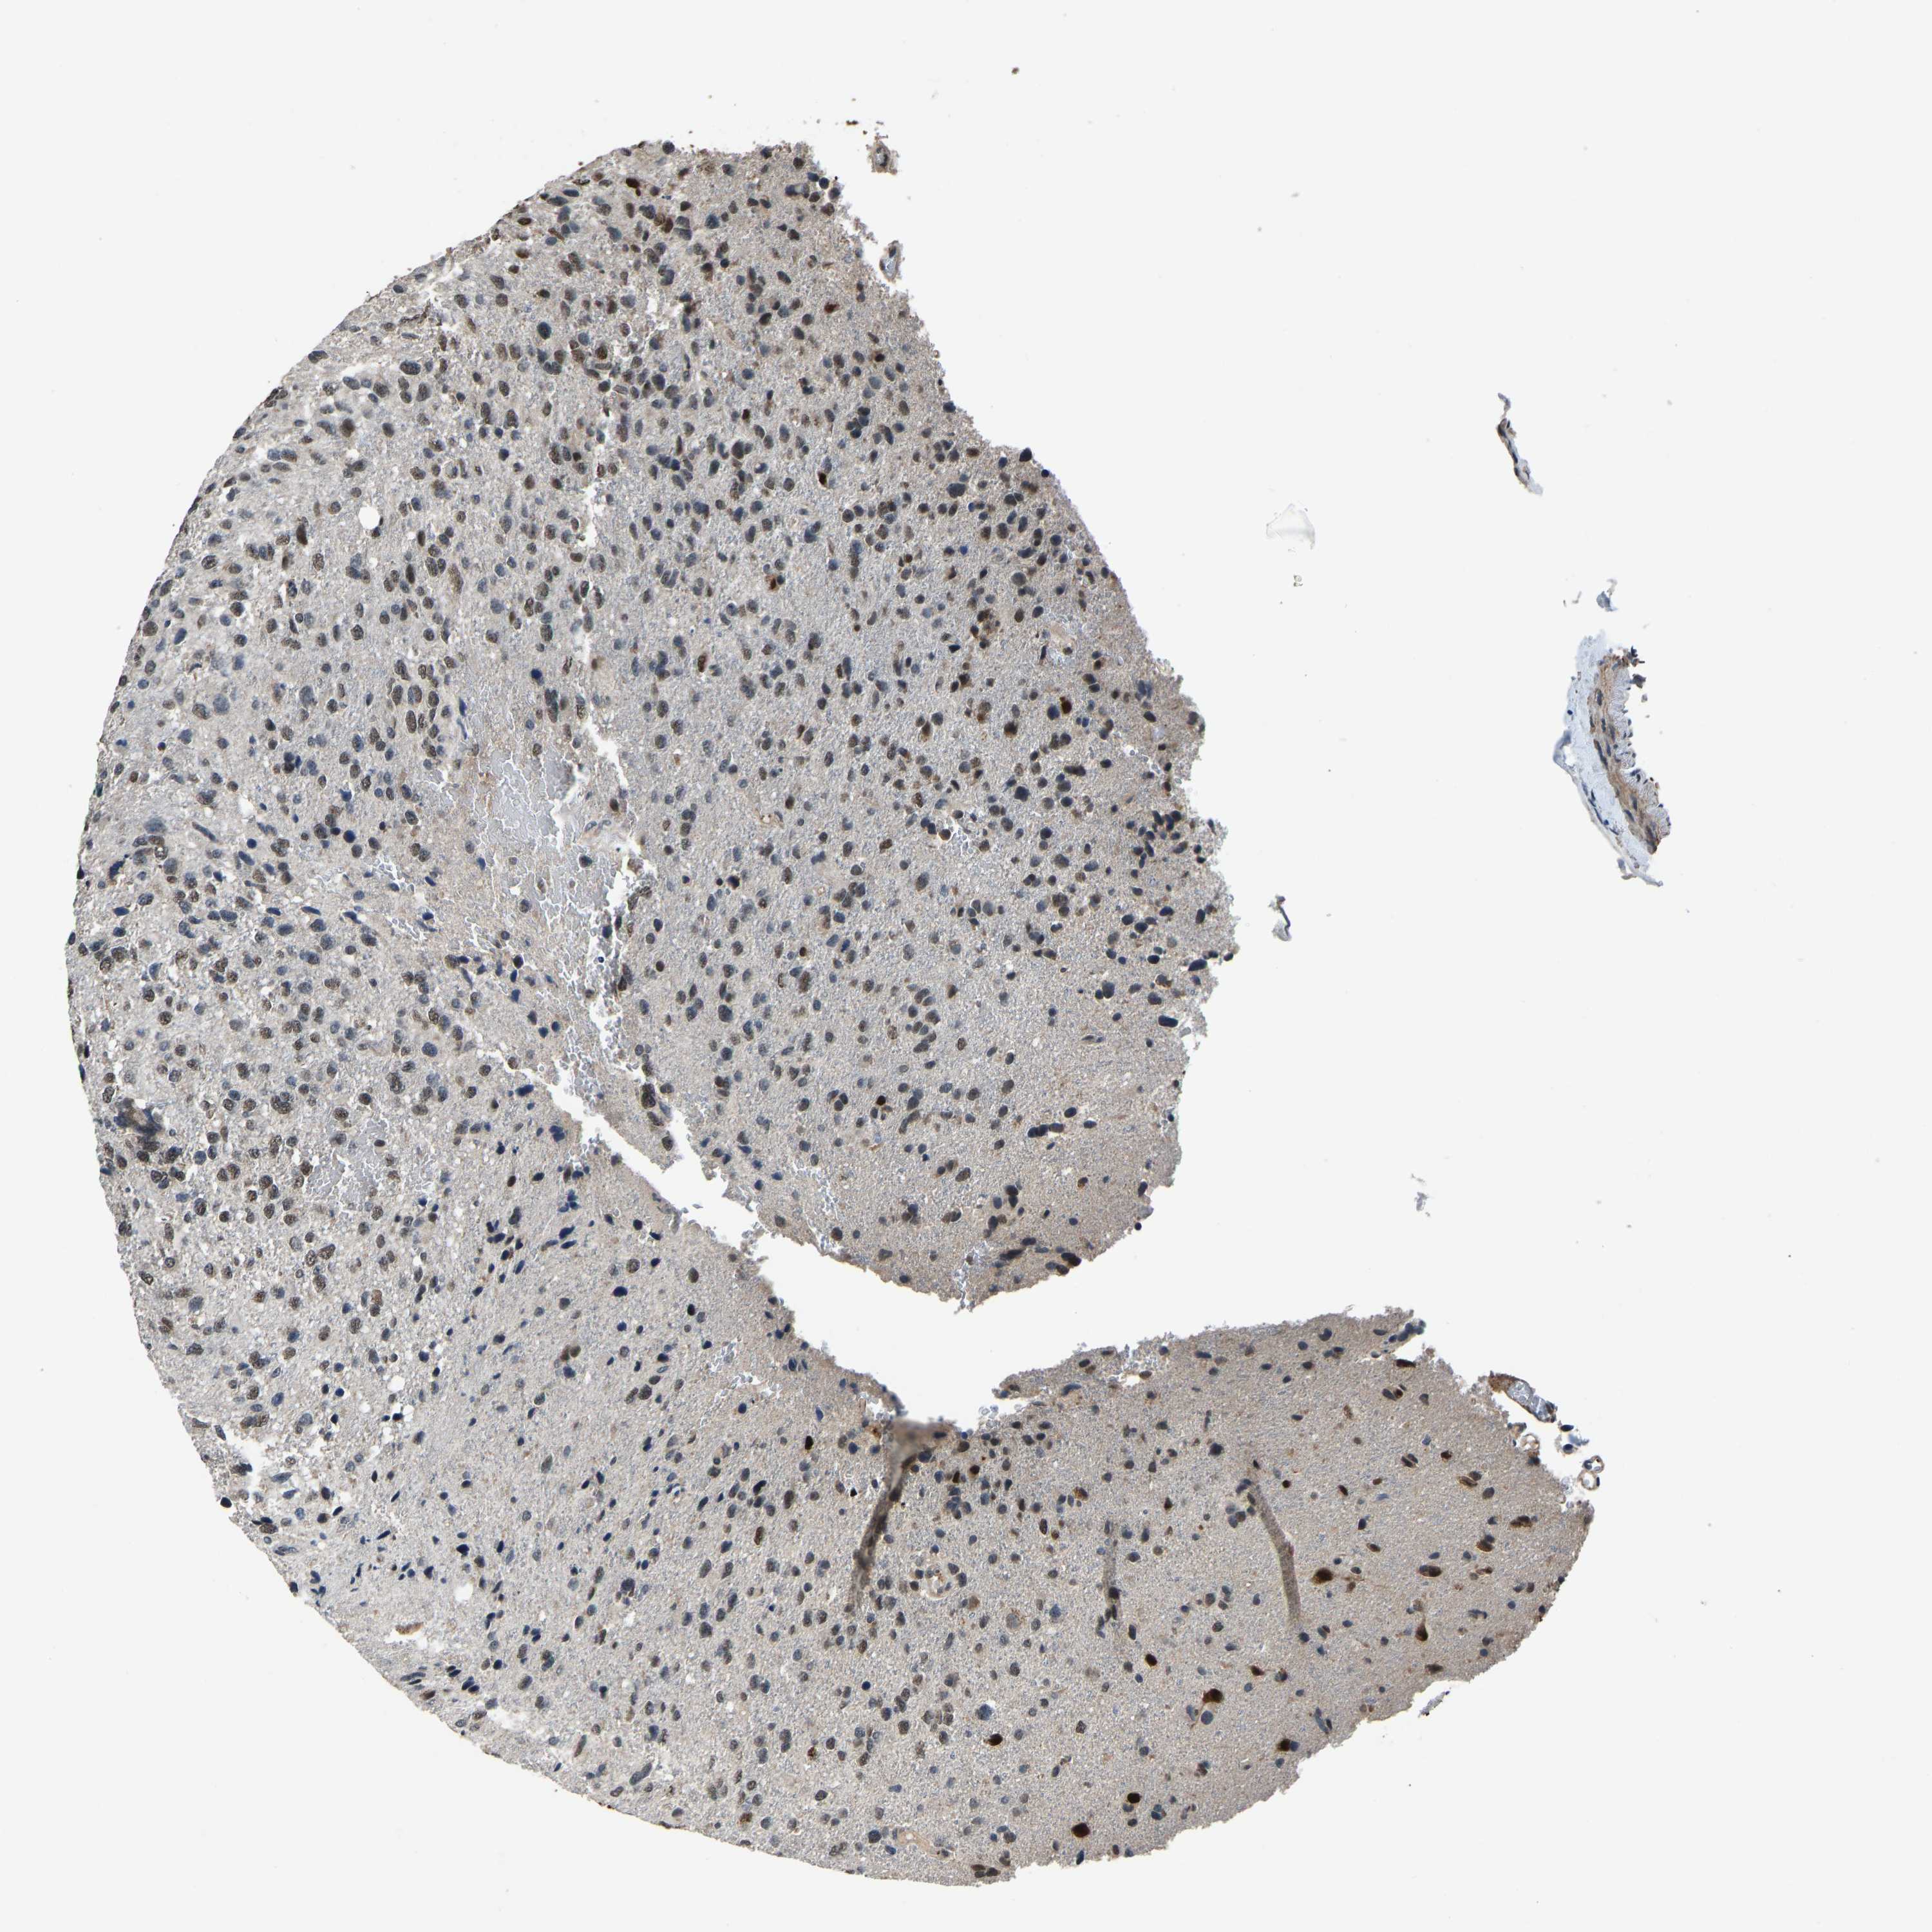

GLIOMA - Protein expressioni

A mouse-over function shows sample information and annotation data. Click on an image to view it in a full screen mode. Samples can be filtered based on level of antibody staining by selecting one or several of the following categories: high, medium, low and not detected. The assay and annotation is described here.

Note that samples used for immunohistochemistry by the Human Protein Atlas do not correspond to samples in the TCGA dataset.

Antibody stainingi

Antibody staining in the annotated cell types in the current human tissue is reported as not detected, low, medium, or high, based on conventional immunohistochemistry profiling in selected tissues. This score is based on the combination of the staining intensity and fraction of stained cells.

Each image is clickable and will lead to virtual microscopy that enables deeper exploration of all samples and also displays staining intensity scores, fraction scores and subcellular localization as well as patient and tissue information for each sample.

Antibody HPA018531

Staining

High

Medium

Low

Not detected

Intensity

Strong

Moderate

Weak

Negative

Quantity

>75%

75%-25%

<25%

None

Location

Nuclear

Cytoplasmic/membranous

Cytoplasmic/membranous,nuclear

Glioma, malignant, High grade

Glioma, malignant, Low grade